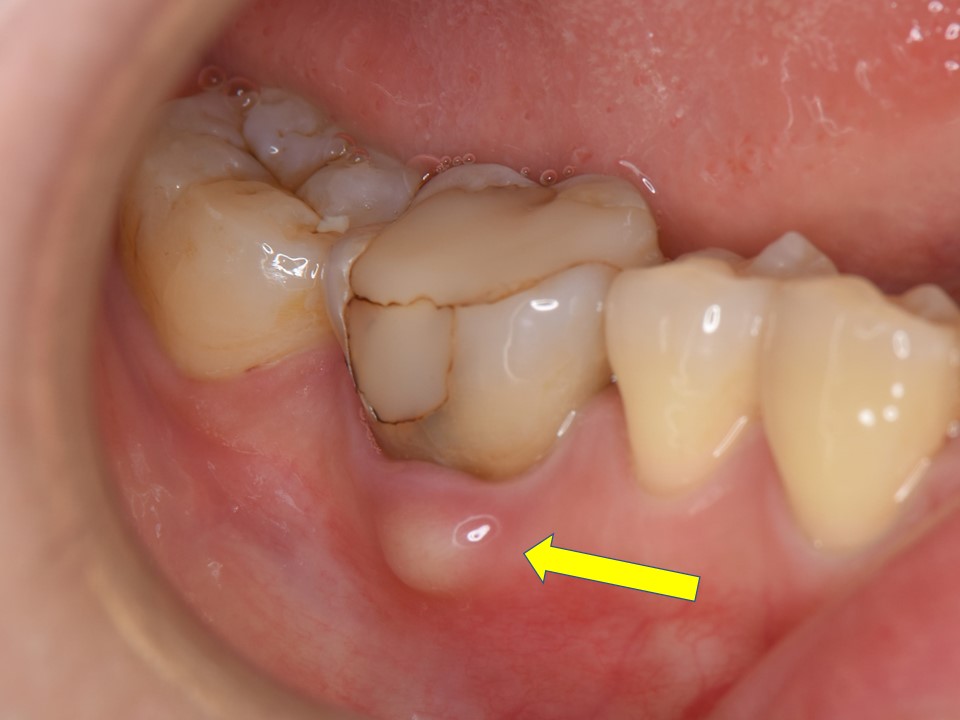

歯周病

歯周炎は、未治療の歯肉炎から発症する可能性がある進行中の歯周病のより重篤な形態です。これは、歯を支える組織や骨を攻撃するプラークの蓄積によって引き起こされる感染症です。そうなると歯ぐきが下がってしまい、歯がグラグラになってしまいます。

歯周炎は通常ゆっくりと進行しますが、急速に発症する場合もあります。主な症状は歯肉の痛みですが、次のような症状も引き起こす可能性があります。

歯周炎の治療には、スケーリングと根の植え付けと呼ばれる高度な専門的な歯のクリーニングが必要です。これらはどちらも歯茎の下から細菌を除去するのに役立ちます。別の感染症を防ぐために、定期的なブラッシングとデンタルフロスを続ける必要があります。